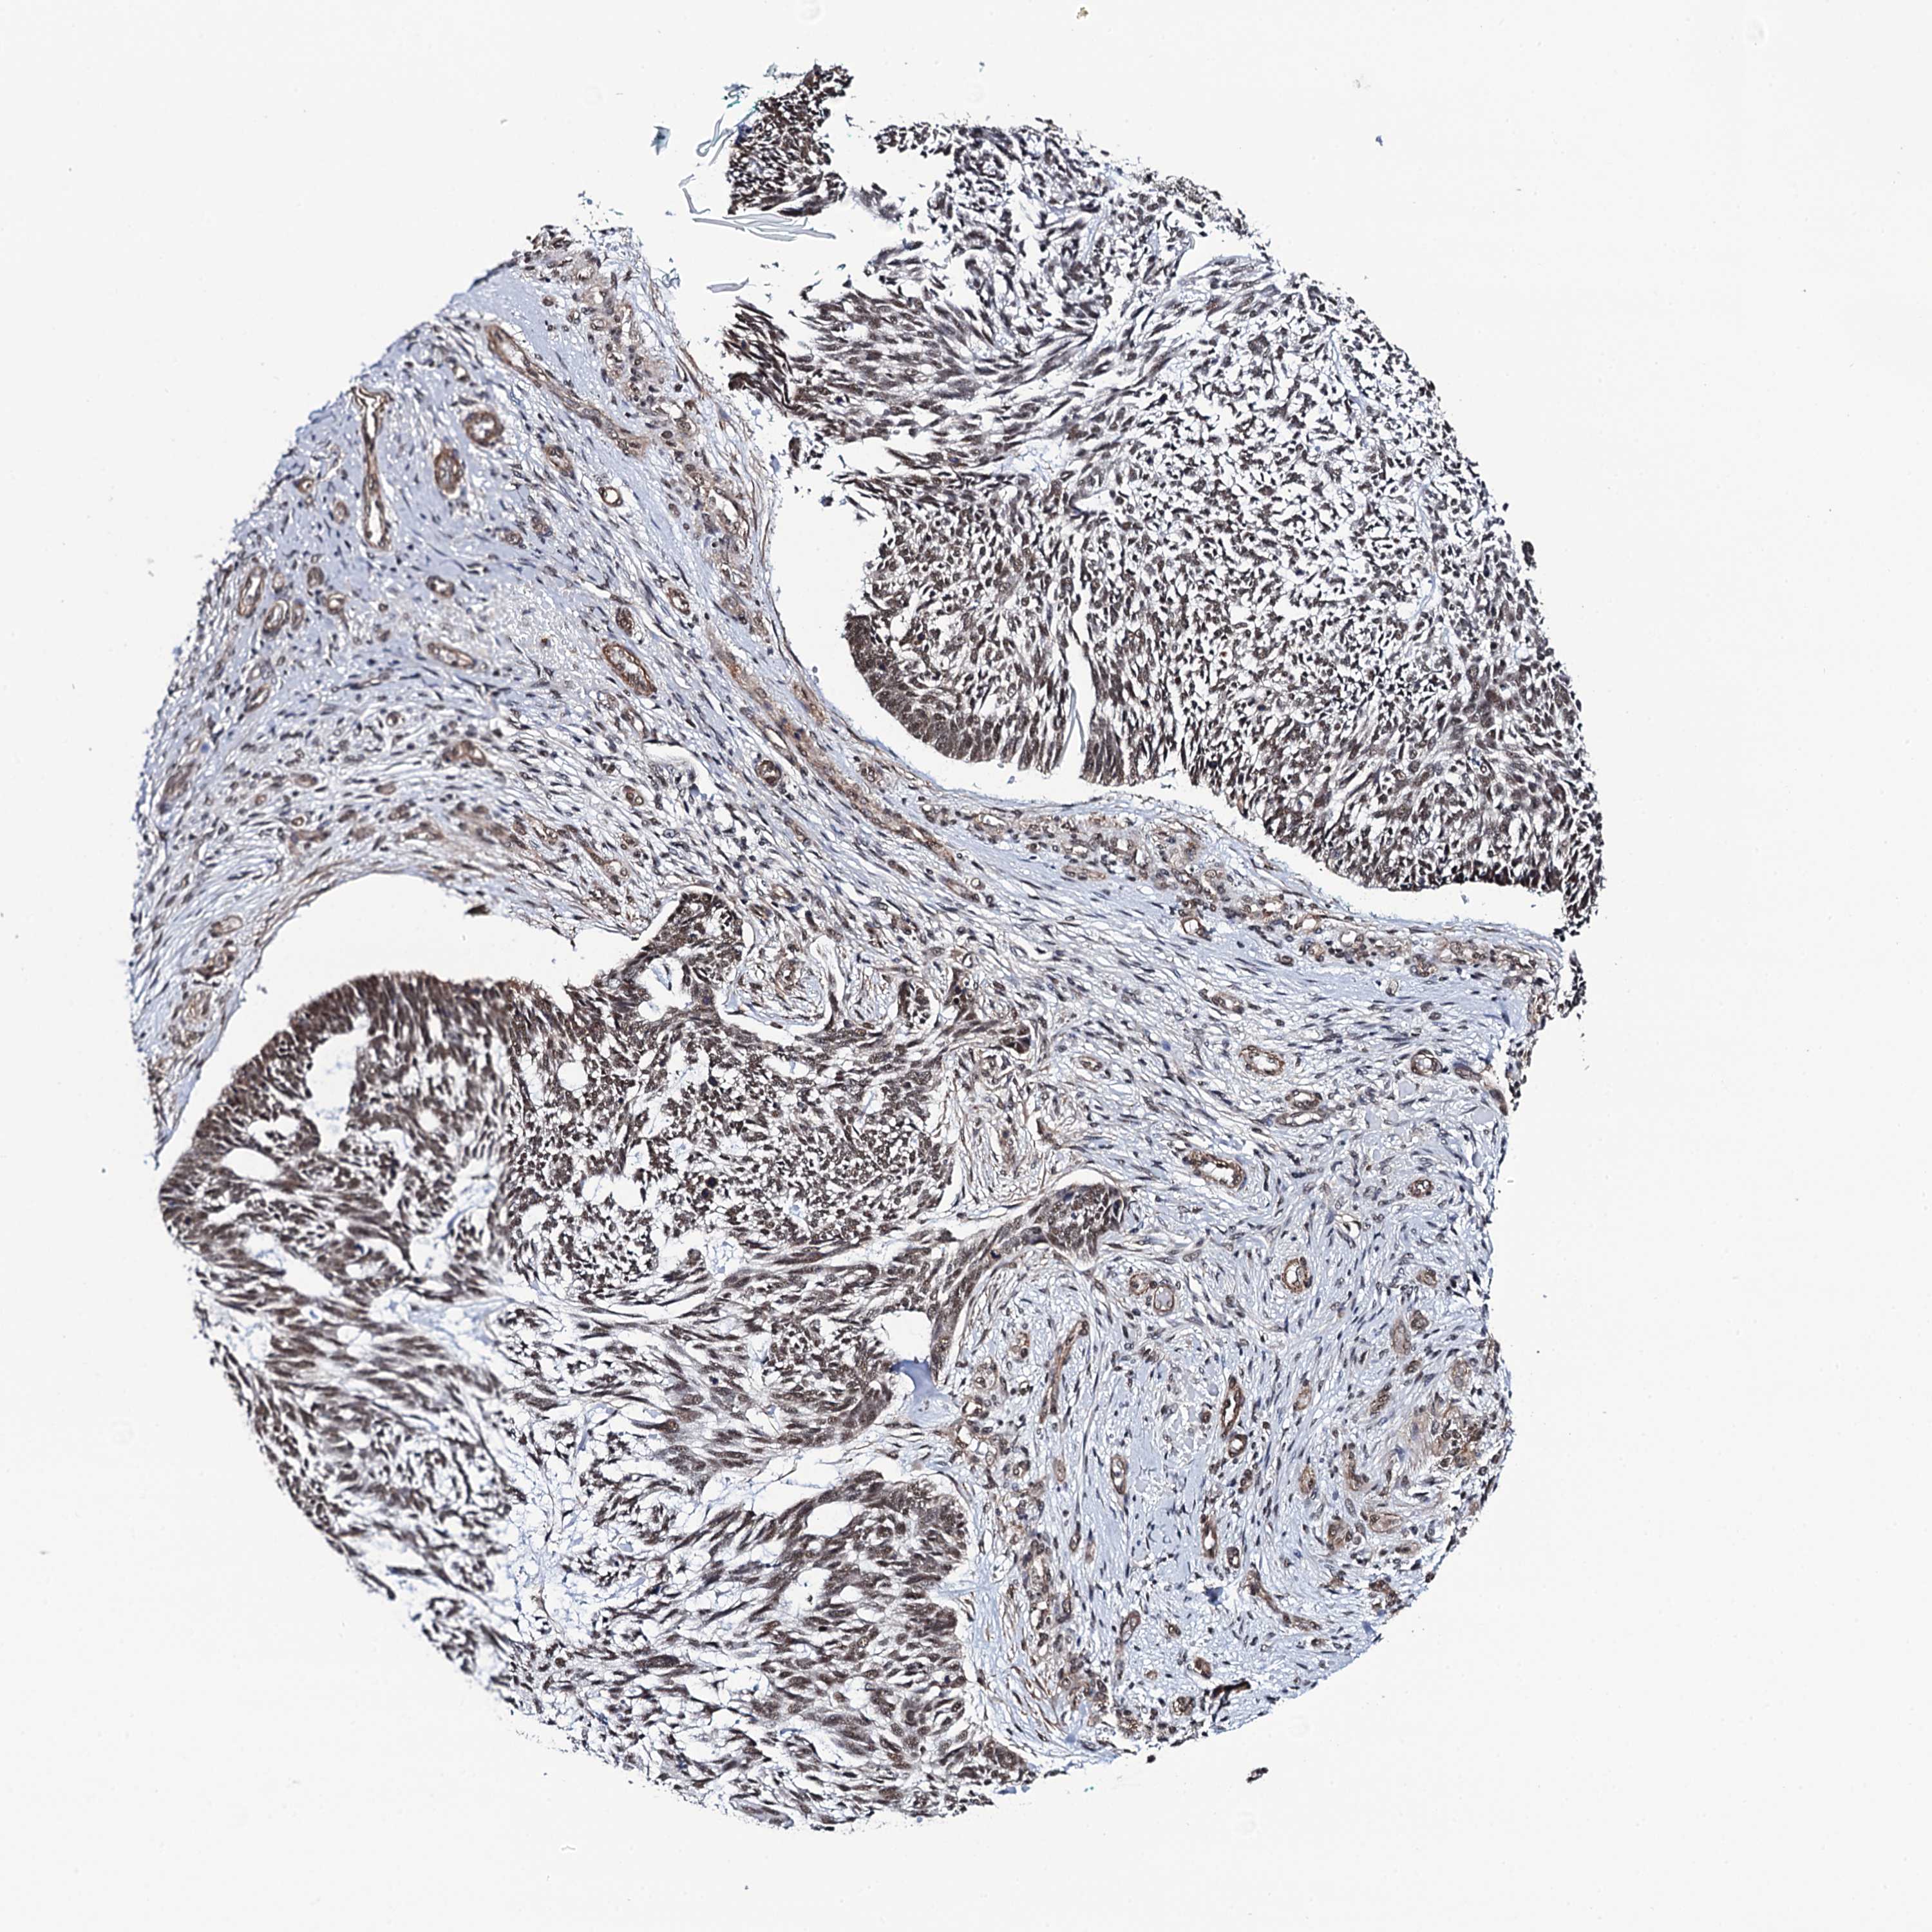

Basal cell and squamous cell cancer

SKIN CANCER - Protein expressioni

A mouse-over function shows sample information and annotation data. Click on an image to view it in a full screen mode. Samples can be filtered based on level of antibody staining by selecting one or several of the following categories: high, medium, low and not detected. The assay and annotation is described here.

Antibody stainingi

Antibody staining in the annotated cell types in the current human tissue is reported as not detected, low, medium, or high, based on conventional immunohistochemistry profiling in selected tissues. This score is based on the combination of the staining intensity and fraction of stained cells.

Each image is clickable and will lead to virtual microscopy that enables deeper exploration of all samples and also displays staining intensity scores, fraction scores and subcellular localization as well as patient and tissue information for each sample.

Antibody HPA039878

Staining

High

Medium

Low

Not detected

Intensity

Strong

Moderate

Weak

Negative

Quantity

>75%

75%-25%

<25%

None

Location

Nuclear

Cytoplasmic/membranous

Cytoplasmic/membranous,nuclear

Squamous cell carcinoma, metastatic, NOS